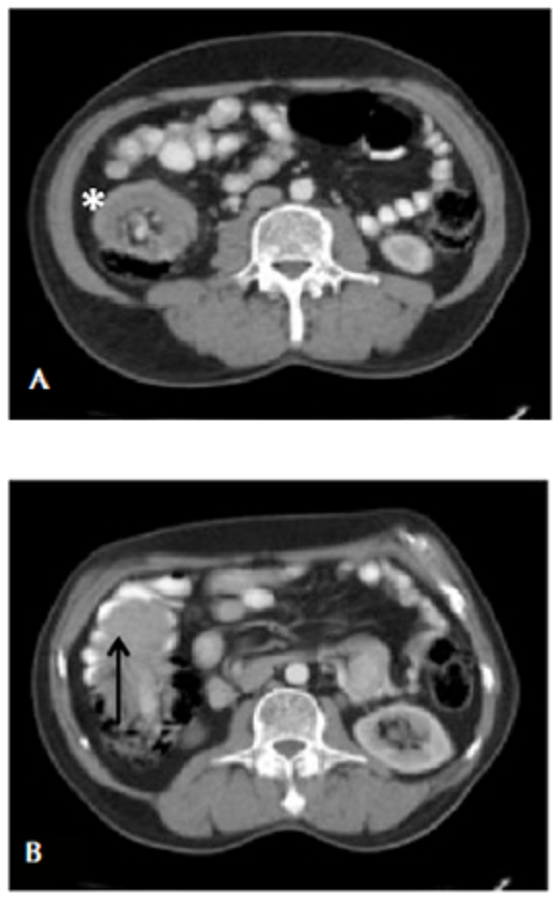

En el examen físico, el abdomen estaba distendido, doloroso a la palpación derecha, sin signos de irritación peritoneal. En el hemiabdomen derecho, se palpaba una masa de 2 x 5 cm de diámetro. En los exámenes de laboratorio no se encontraron anormalidades. En la radiografía abdominal no se observó dilatación de asas. En la TC abdominal se apreció una masa de contornos lobulados en la región ileocólica, con intususcepción de 4,8 x 5 cm, con el ‘signo de la diana’ presente (figura 4).

La TC es la modalidad de imagen de elección para el diagnóstico de intususcepción en los adultos. En esta técnica, se presenta como una masa en forma de salchicha en el corte longitudinal y como una masa en diana en el corte transversal, por el efecto de la pared intestinal y el mesenterio dentro de la luz, tal como se presenta en el segundo caso 23. Su rango de precisión diagnóstica es del 58 % al 100 % 24,25. Autores como Azar y Berger informan que la TC abdominal diagnostica con precisión la intususcepción intestinal en 78 % de los pacientes 1.